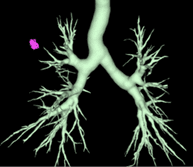

Reconstructions 3D

De quoi s’agit-il ?

Nous reconstruisons l’anatomie du patient en 3 dimensions grâce à un scanner thoracique (en utilisant le logiciel Synapse 3D) avant l’opération afin de la préparer car chaque patient est unique et chaque anatomie est différente.

A quoi ça sert ?

Les reconstructions 3D permettent au chirurgien de :

- diminuer la durée de l’intervention chirurgicale grâce à un gain de temps de dissection

- planifier le déroulé de l’intervention chirurgicale, c’est-à-dire , prévoir les étapes de dissection de l’organe

- réaliser des interventions plus complexes qu’auparavant grâce à une meilleure précision de la connaissance de l’anatomie du patient qui est soigné

- diminuer le risque d’erreur anatomique pendant l’opération quand les patients ont une anatomie inhabituelle

- diminuer le risque d’accident hémorragique lors de l’intervention

- améliorer les marges de résection de sécurité d’une tumeur en augmentant ainsi la qualité oncologique du geste